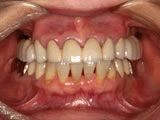

当院では1987年にITIストローマンインプラントによる部分欠損への応用、 また1989年にブローネマルクインプラント用いた無歯顎インプラント治療 (歯がすべてなくなった人へのインプラント治療)を開始しました。

現在までに約2000本のインプラント治療を34年ほど前から行っております。当時はインプラント治療といってもまだ一般的ではなく、「そんな治療聞いたことがない」とおっしゃる患者様が多く、インプラント治療をお受けになる方は少なかったです。最近では「私の場合はどんな治療がいいのですか?入れ歯かインプラントかどっちがいいですか?」と、ご相談にいらっしゃる患者様が増えています。

昨今、人体の再生医療の進歩には目を見張るものがあります。それに伴い骨の再生の研究が進み、インプラント治療も進化しつづけております。1980年代以後、現在に至るまで世界中でいろいろなインプラントが開発されております。その中から当院では現在ブローネマルクインプラント、ライフコアーインプラント、 スプラインインプラント、GCインプラントなどのインプラントを使用しております。

インプラント治療にはいろいろなご意見があります。歯がなくなった方、すべての患者様においてインプラント治療が一番良いというわけではありません。正しい診査診断により決定すべきです。しかし、インプラント治療が歯科医学的に良いとか悪いとかと言う議論をする時代ではなくなりました。 インプラント治療は歯の欠損修復治療として確立されたと言えるでしょう。